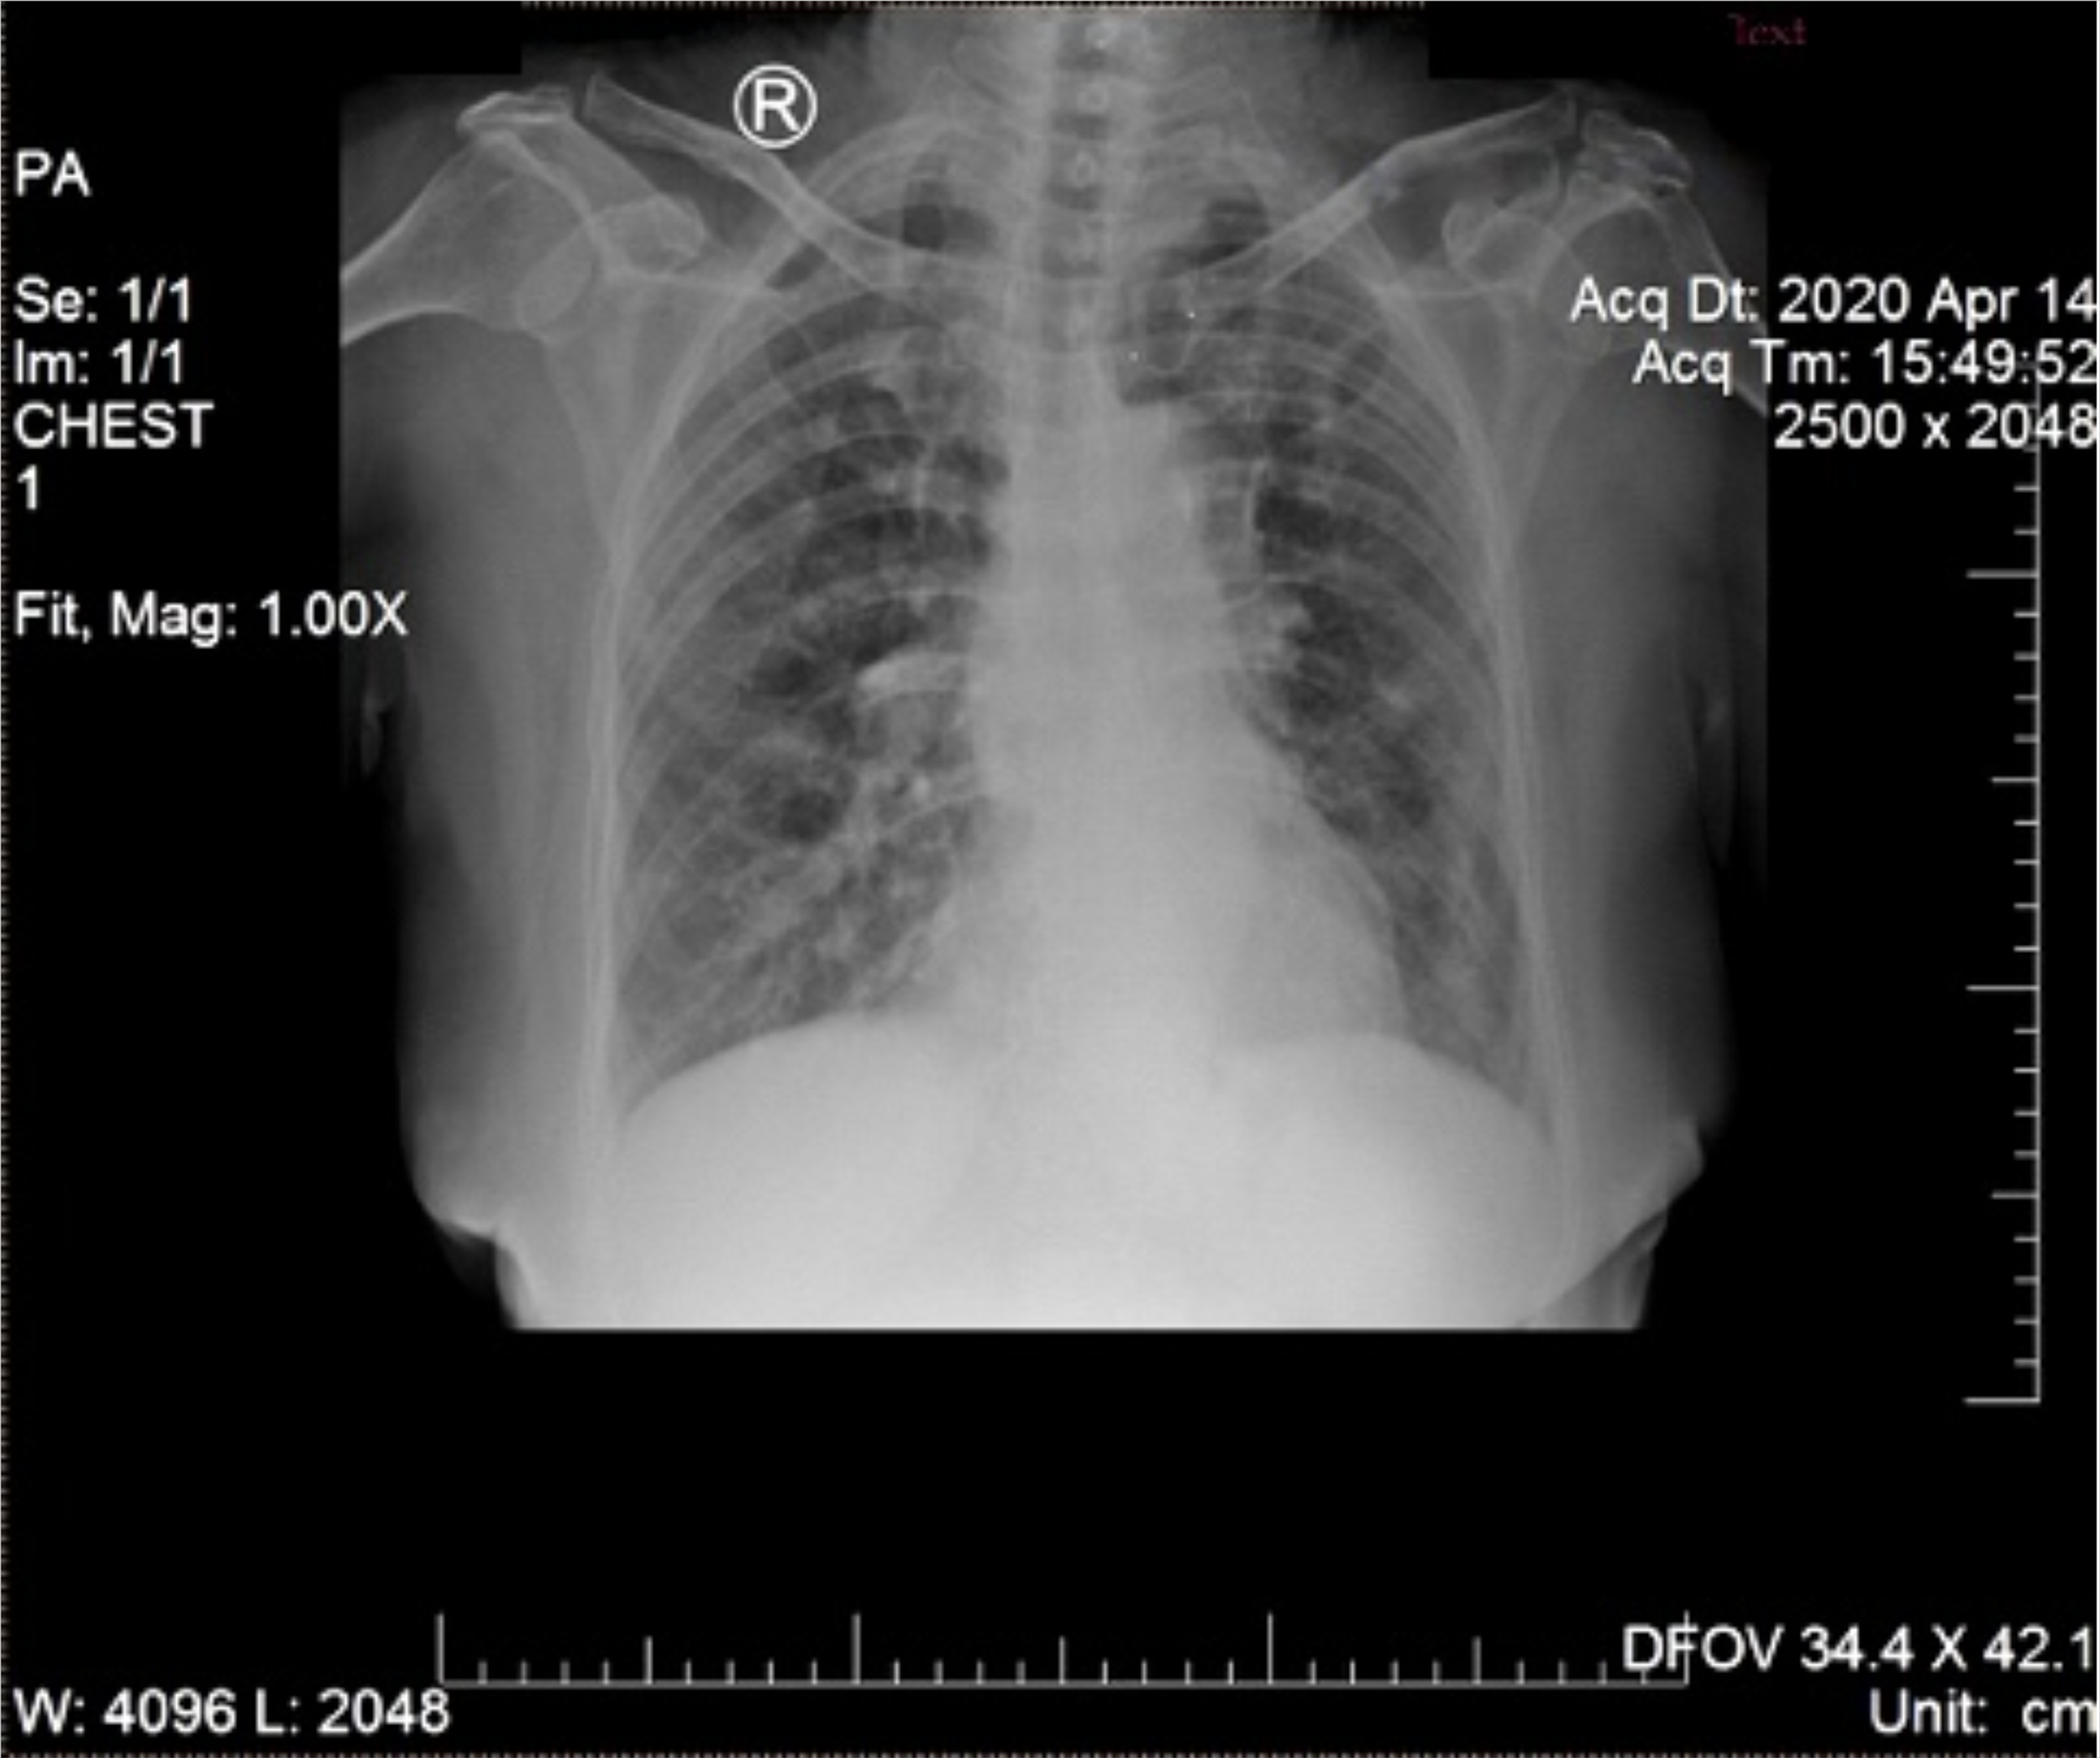

A 68-year-old woman with chronic diabetes mellitus type II was referred to Tangerang District Hospital on 14 April 2020 by a general practitioner with a clinical diagnosis of dengue fever. She presented with five days of fever to 39°C managed with oral antipyretics, accompanied by malaise, anorexia, nausea, myalgia, and arthralgia. Cough and diarrhea had appeared one day later. She reported living in a neighborhood where a few people were contracting dengue fever and participating in a religious gathering four days prior to symptom onset. On exam, vital signs were within normal limits, except for mildly elevated blood pressure (150/90 mmHg). No rash or bleeding was observed. Chest X-ray (CXR) showed right pericardial infiltrates, suggesting bronchopneumonia (Figure 1). Hematology results revealed anemia (hemoglobin 10.9 mg/dL), thrombocytopenia (99,000/mm3), normal leukocyte count (8,000/mm3), increased neutrophil proportion (78%), decreased lymphocyte proportion (13%), and decreased absolute lymphocytes (1040/mm3). Her random blood sugar, ureum and creatinine levels were normal (110 mg/dL, 24 mg/dL, and 0.8 mg/dL, respectively). She was taking glibenclamide, and had no history of heart or kidney disease.

Figure 1

Chest X-ray on day of hospitalization. Pericardial infiltrates suggest bronchopneumonia.

When our case occurred, RDTs for the SARS-CoV-2 antigen were not available, as reflected by the assessments of the general practitioner and emergency room physician, both of whom suspected dengue based on clinical presentation and ongoing local transmission of DENV. Along with a high index of suspicion, epidemiology, clinical symptoms, laboratory testing, and imaging enable diagnosis of COVID-19 (27). Radiography, including CXR, is performed to screen suspected cases according to the COVID-19 diagnosis and management guidelines from Indonesian Society of Respirology. CXR findings of multiple bilateral ground-glass opacities in the peripheral lower lung zone and pericardial infiltrate may help distinguish COVID-19 from dengue, the latter of which may present with pleural effusions (34, 36). Subsequently, the pulmonologist suspected COVID-19 despite the existing DENV clinical diagnosis in light of the consistent respiratory, laboratory, and imaging findings. It was then discovered that the patient had contact with a confirmed COVID-19 case 4 days prior to emergence of symptoms.